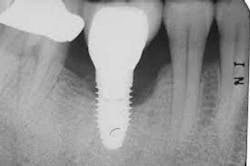

Peri-implantitis, including peri-implant mucositis and peri-implantitis, is a common cause for the failure of dental implants. Failure can be initiated by inappropriate treatment planning, surgical or mechanical failure, or poor maintenance.(1) Risk factors are many, and include poor biofilm plaque control and/or the inability of a person to cleanse the area adequately. There are many different treatments for managing peri-implantitis.

A Cochrane Systematic Review aimed to identify the most effective interventions for treating peri-implantitis.(3) They concluded that there is no consistent evidence that any one treatment modality is superior to another, however, that does not mean that any of the treatments are ineffective. Another 2014 Systematic Review did not offer any specific recommendations; they did report some successful outcomes.(4) Problems with recommendations include a variety of definitions being used in the studies, varying disease severity, different lengths of time for follow-up, and differing inclusion/exclusion criteria.